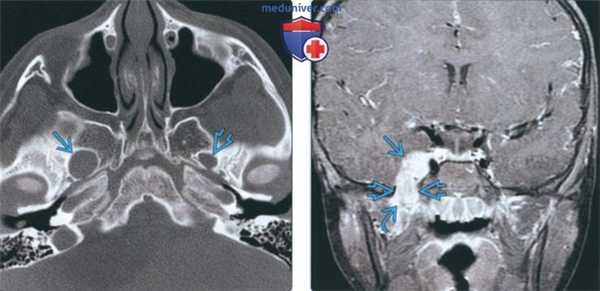

(Слева) На аксиальной КТ в костном окне у пациента с известным нейрофиброматозом 2 типа определяется расширение правого овального отверстия. Обратите внимание на неизмененное овальное отверстие слева. Такое расширение отверстий с сохранением их краевых кортикальных пластинок характерно для доброкачественных опухолей оболочки нерва.

(Справа) На корональной МРТ (Т1 ВИ С+ FS) у этого же пациента визуализируется шваннома ЧМН V3 вытянутой формы, накапливающая контраст. Опухоль начинается в параселлярной области, выходит через расширенное овальное отверстие в жевательное пространство на уровне носоглотки.